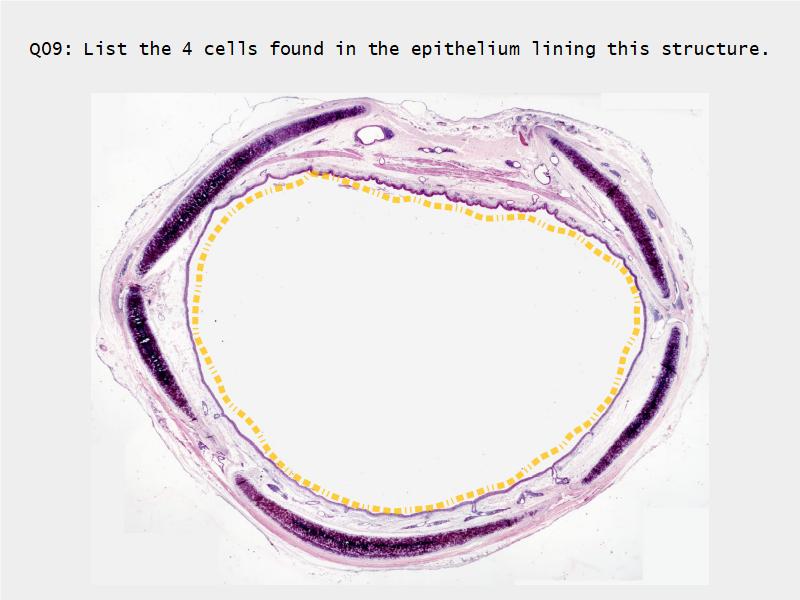

Respiratory epithelium

- Pseudostratified

- Ciliated

- Columnar

- Epithelium with

- 4 Cells

- Ciliated columnar cells

- Non-ciliated columnar cells

- Goblet cells

- Basal cells